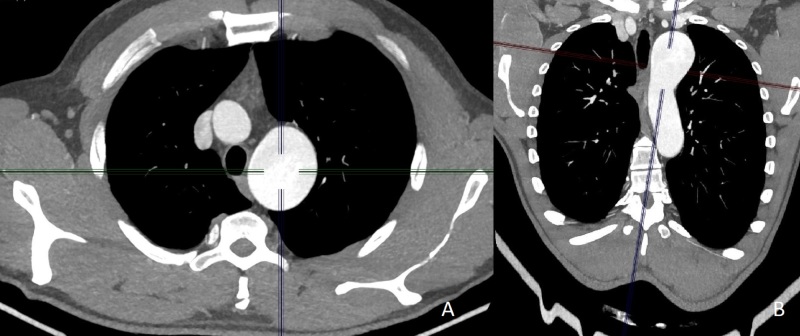

Aortic arch aneurysms are often asymptomatic, being diagnosed incidentally in tests such as computed tomography, magnetic resonance imaging, or echocardiogram. Conventional treatment involves thoracotomy surgery, although treatment can also be performed using endovascular techniques. This article presents a case report of a complex aneurysm of the aortic arch with involvement of the left subclavian artery. Treatment was initiated with debranching of the supra-aortic trunks by carotid-carotid and carotid-subclavian bypasses, followed by ligation of the common carotid and left subclavian arteries. A second procedure was then needed to construct a surgical vascular conduit using a Dacron graft to obtain access to the aortic arch for the stent graft delivery device, due to the narrow caliber of the external femoral and iliac arteries. This report illustrates a satisfactory outcome in a case of aortic arch aneurysm with complex anatomy.